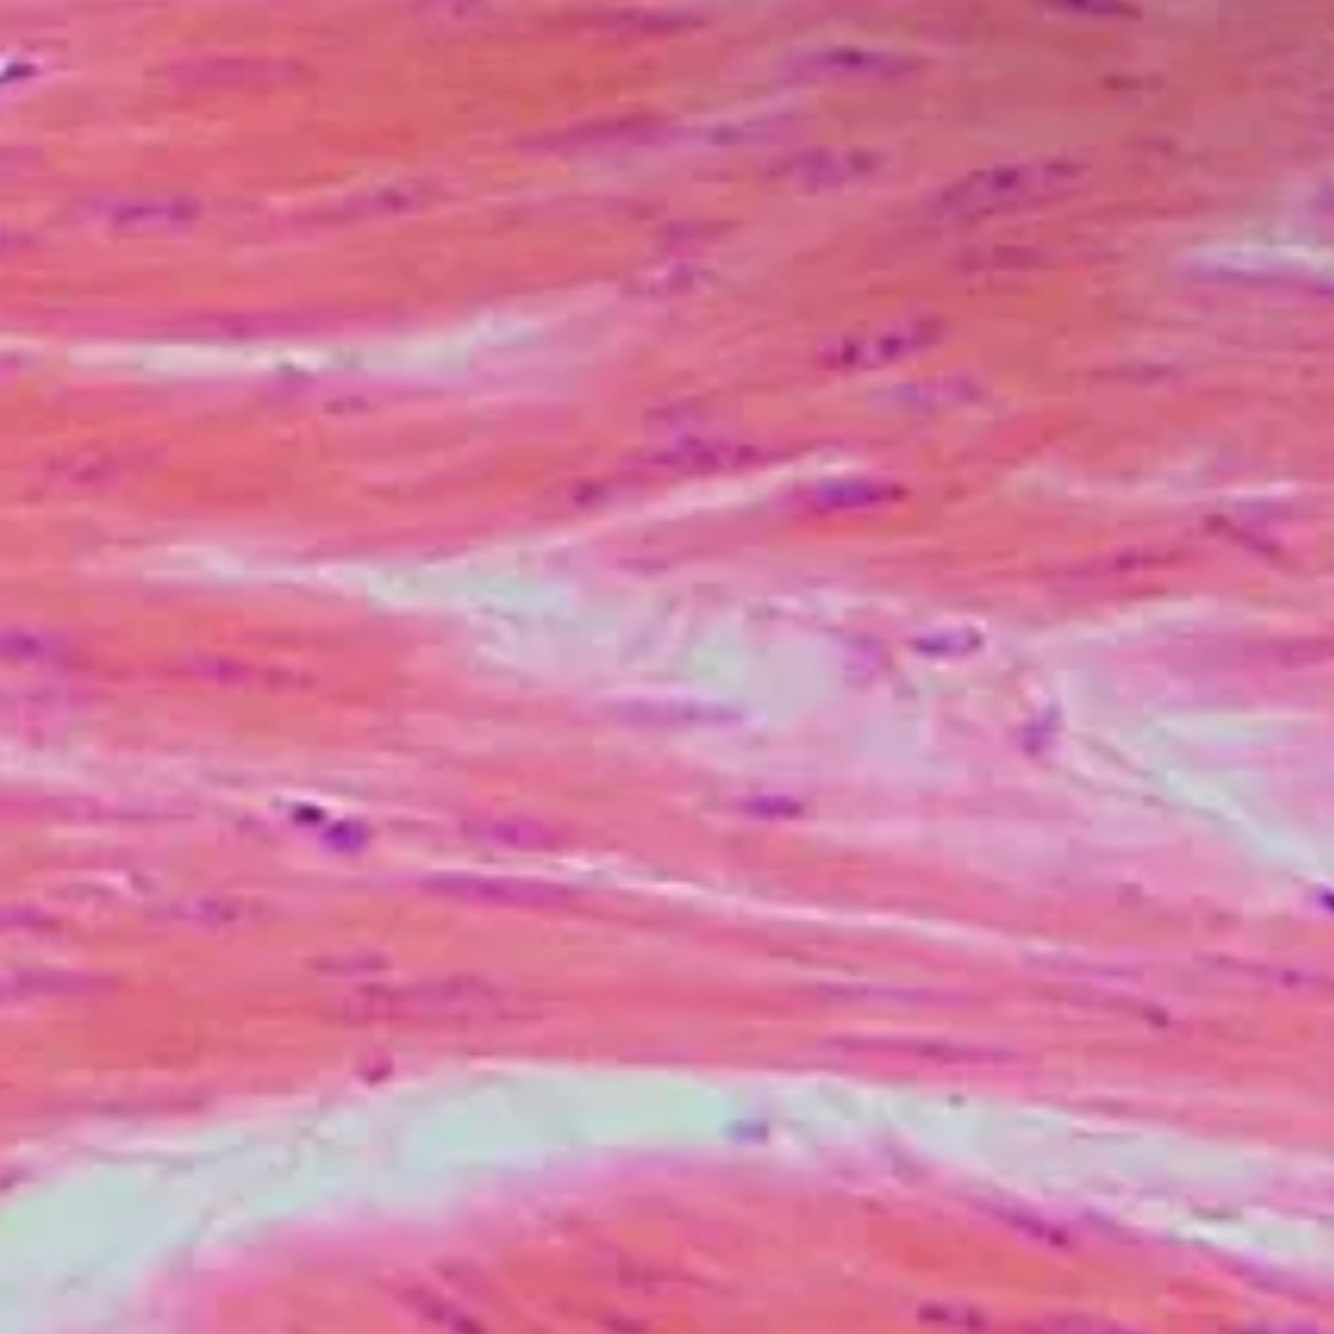

1.Dense Elastic Tissue

2. Arteries/ bronchial

3. Tensile strength, Recoil